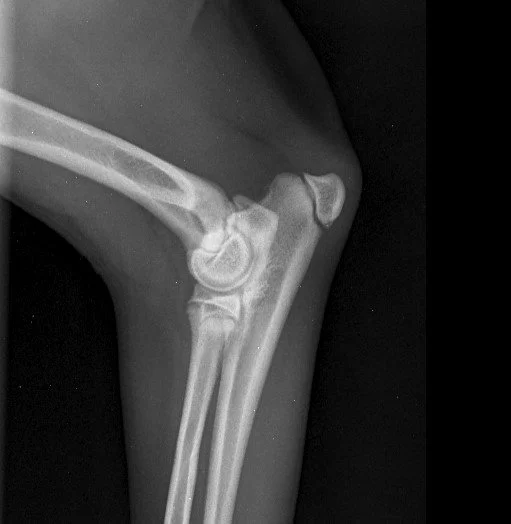

Early Diagnosis of Hip & Elbow Dysplasia in Dogs

Hip and elbow dysplasia are among the most common skeletal orthopedic diseases affecting growing dogs and can significantly impact a dog’s quality of life. They involve malformation of the joints, leading to an imbalanced load distribution within the joint and, consequently, to cartilage erosion, inflammation, and arthrosis.

2)      Diagnostic imaging: x-ray under sedation, in some cases combined with CT scan to assess joint conformation minimal joint surface defect (especially in the elbow joint where radiology is indicated for initial assessment but not sensitive enough to confirm the diagnosis).